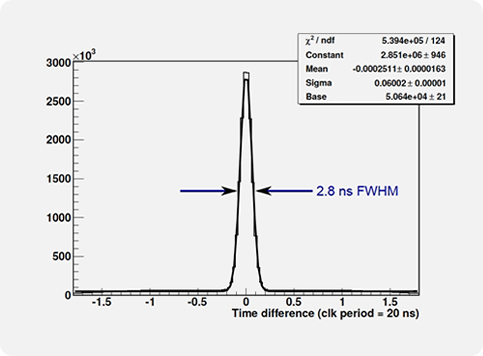

The main spectroscopic characteristics of the Clear-PEM system are energy resolution for 511 keV photons of of 13.4%, coincidence time resolution of 2.8 ns (FWHM) and DoI resolution of 2.8 mm (FWHM).